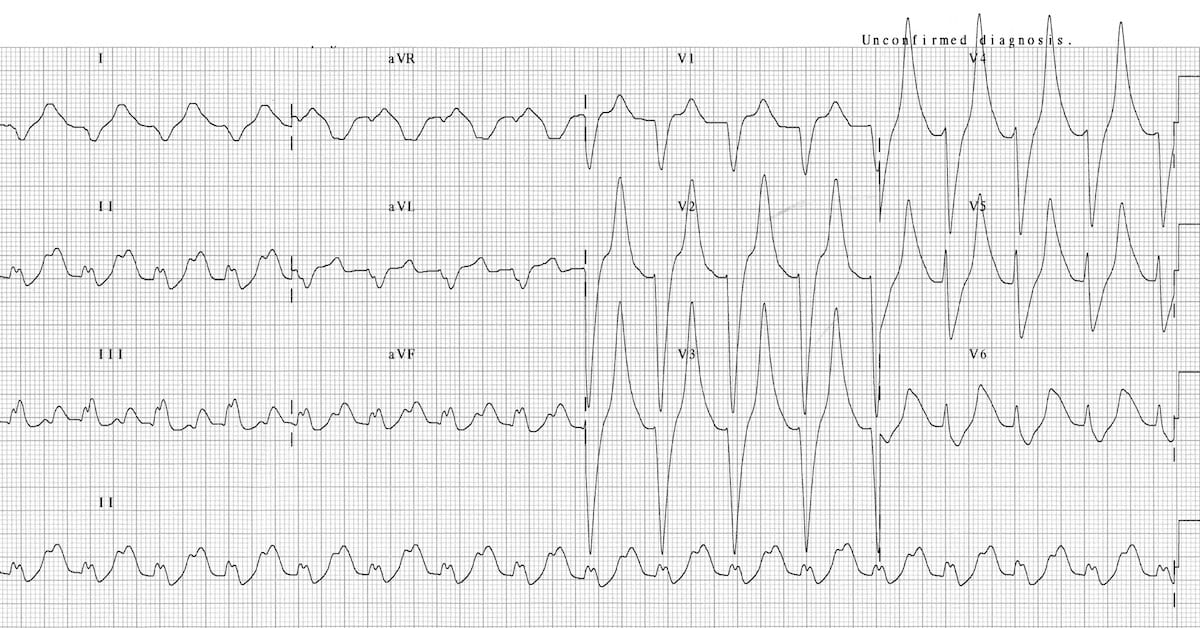

This is an ECG of non-sustained ventricular tachycardia. There are 4 consecutive PVCs, then 3 consecutive PVCs.

© Life in the Fast Lane. Licensed under CC BY-NC 4.0